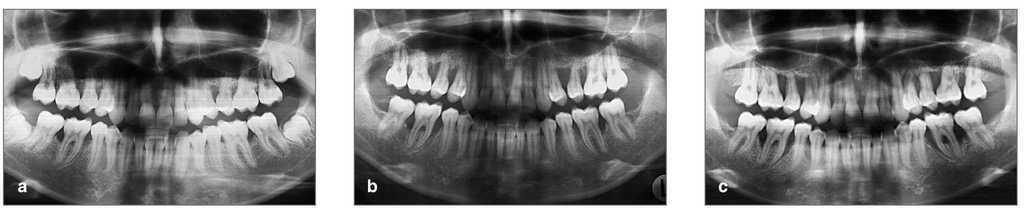

Se presenta el caso de una mujer que presentaba periodontitis agresiva de 14 años de evolución. De 1993 a 2000, no se sometió a ningún tratamiento periodontal pero la progresión de la enfermedad pudo reconstruirse a partir de los registros radiográficos anteriores. Las radiografías de 1993 (fig. 1a), cuando la paciente presentaba 16 años de edad, mostraron pérdida ósea localizada en los premolares superiores de aproximadamente el 50% y defectos intraóseos localizados en los primeros molares inferiores derecho e izquierdo del 30% de longitud de las raíces. Estos defectos aumentaron en 1996 al 70% en los premolares superiores y al 50% en los molares inferiores (fig. 1b), y en 1999 hasta el 90% en los premolares superiores y 75% en los molares inferiores con afectación de furca (fig. 1c). Todo ello indicaba una rápida progresión de la enfermedad con una pérdida anual de hueso de aproximadamente 2 mm.

Figuras 1a a 1c. Radiografías de (a) 1993, (b) 1996 y (c) 1999 que muestran la progresión de la enfermedad.

Desde entonces, se ha venido realizando tratamiento periodontal de mantenimiento cada tres meses. En 2007, cuando la paciente contaba con 31 años de edad, las radiografías mostraron, en los primeros molares inferiores, una regeneración casi completa de los defectos anteriores hasta un nivel óseo similar al de los dientes adyacentes (figs. 3a a 3c). Los premolares superiores seguían manteniéndose y presentaban un cierto grado de regeneración ósea.

Figuras 3a a 3c. Estado radiográfico detallado y situación clínica en el año 2007 después de tratamiento de desinfección a boca completa y procedimientos de regeneración quirúrgica.